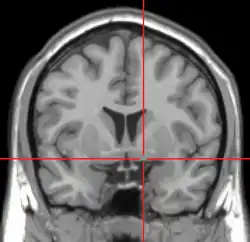

![]() Coronal MRI slice with cross-hairs indicating location of the substantia innominata | |